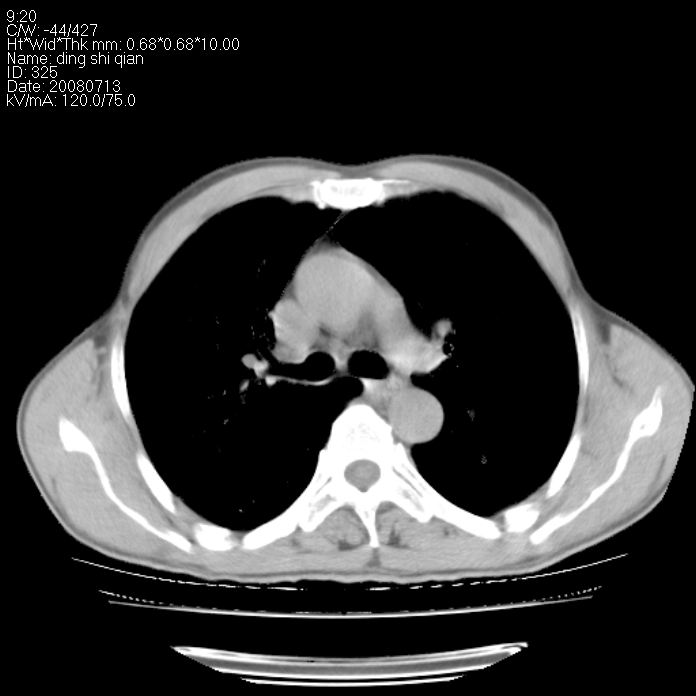

标题: CT14654:男 50岁 近来胸痛 [打印本页]

标题: CT14654:男 50岁 近来胸痛

右侧上肺块状软组织影,浅分叶,边缘毛刺证,与胸膜粘连,考虑:周围性肺癌

右肺上叶周围型肺癌可能性大。

右侧上肺块状软组织影,浅分叶,边缘毛刺证,与胸膜粘连,考虑:周围性肺癌!支持!

首先考虑周围性肺癌,建议强化或穿刺明确